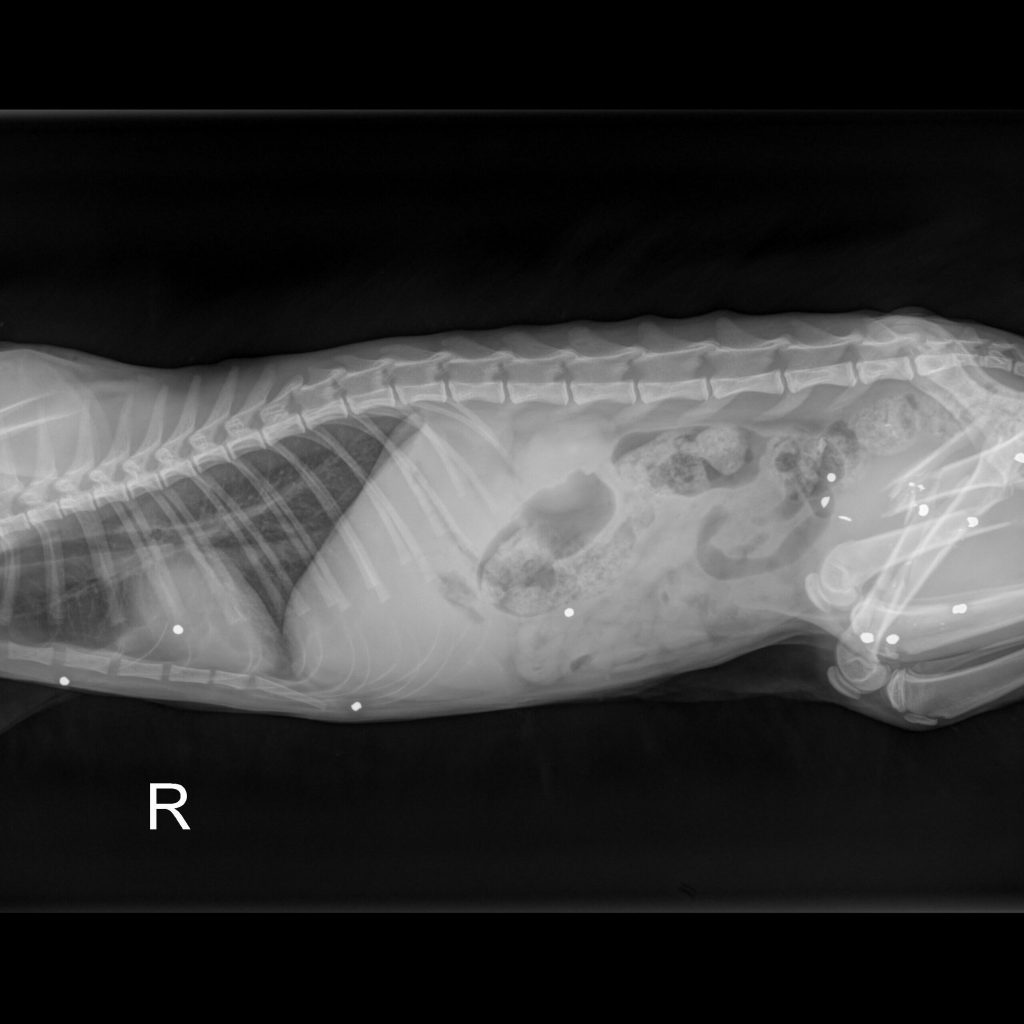

Today this cat arrived at the Richmond SPCA, and we named her Miracle. While Dr. David Molinas, our associate veterinarian, looked her over, she purred and made biscuits on the exam table with a level of affection that disguised the pain she must be experiencing. Radiographs from River Run Animal Hospital, where she was given supportive care yesterday, show metallic fragments that are likely birdshot scattered throughout her body, most highly concentrated in her pelvis and hind limbs. Both of her femurs, the large upper bones of the rear legs, are broken.